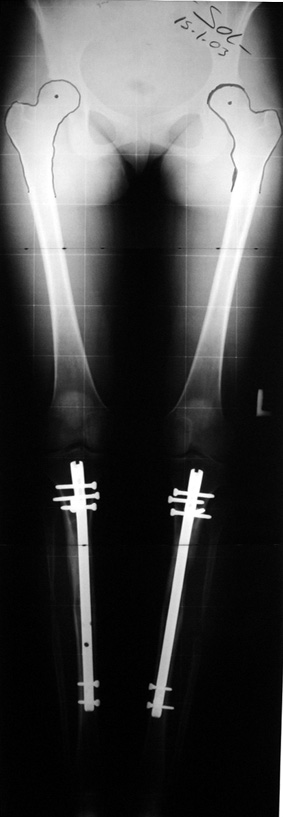

Biz son zamanlarda, seçilmiş vakalarda, uzatma sonrası uzunluğu ve “alignment’ı” korumak amacı ile unilateral dinamik aksiyel fiksatör ve kilitli intramedüller çivi kombinasyonunu tercih etmekteyiz. Bu yöntemin ön şartları medullanın en dar çapının 7 mm.’den geniş olması ve uzatma sonrası distalde en az 8 cm. uzunluğunda çivi kalabilmesidir. İntramedüller çivi hem uzatma esnasında femurun üzerine gelen makaslama ve bükülme kuvvetlerini nötralize etmekte hem eksternal fiksasyon süresini kısaltmakta, hem de yeni oluşan kemiği kırıklara karşı korumaktadır. Serimizde bir vakada subtrokanterik femoral osteotomi yapılmıştır. İntramedüller çiviye rağmen varus angulasyonu oluşması yönünde bir dezavantaj tespit etmedik.

İlizarov, distraksiyon osteogenezisi için endosteal kan dolaşımının önemini vurgulamıştır. Biz tüm vakalarımızda femuru oyarak intramedüller çiviyi çaktık; buna rağmen hiçbir vakada kallus oluşma süresi tahminimizden daha uzun olmadı. Bu yüzden medüller dolaşımın bozulmasına bağlı yeni kemik oluşma hızında bir yavaşlama olmadığını düşünüyoruz. Oyma sonrası meydana gelen revaskülarizasyon, intramedüller çivili fiksasyon stabilitesi ve erken fonksiyonel yüklenme bu gerçeğin temelini oluşturmaktadır. Eksternal ve internal fiksasyon yöntemlerinin kombine kullanımının potansiyel dezavantajları kan kaybının artması, intramedüller infeksiyon, yağ embolisi olasılığı ve aşırı metal yüküdür. Bunların içinde en çok korkulan problem bir çivi dibi infeksiyonun tetikleyeceği derin intramedüller infeksiyondur (panosteomyelit). Bizim serimizde bu yönde hiçbir komplikasyon gelişmemiştir. Bu olası komplikasyonun önlenmesi amacı ile uzatma sonundaki kilitleme medialden yapılmalıdır; ayrıca intramedüller çivi ve eksternal fiksasyon pinlerinin teması önlenmelidir.

Örnek sayılarının az olmasına rağmen etyolojik faktör, yaş, patolojinin yerleşim yeri, miktarı gibi faktörler yönünden benzer iki grubu karşılaştırmayı amaçladık. Eşlik eden tibial uzatma, osteotomi yeri gibi ayrıntıları bu ilk çalışmada göz ardı ettik. Prospektif randomize karşılaştırmalı bioistatistik analiz yapmamız için örnek sayımız azdır. Bu çalışmanın sonuçları matematiksel olarak anlamlı istatistik veriler içermese de belirli bir tecrübenin aktarılması yönünde ülkemizdeki ilk ve tek örnek olduğuna inanıyoruz.

İntramedüller çivi ve eksternal dinamik aksiyel fiksatör kombinasyonu teknik olarak standart İlizarov uygulamalarından daha zordur. Ancak şu avantajlar yöntemi cazip hale getirmektedir; eksternal fiksasyon süresinde kısalma, refraktüre karşı korunma, erken rehabilitasyon, azami hareket genişliği kazanma ve günlük yaşam konforu. Bu avantajlar artan maliyet , artan kan kaybı ve potansiyel derin infeksiyon gibi dezavantajların önüne geçmektedir. Sonuç olarak, bulgularımızın eşliğinde, intramedüller çivi üzerinden femoral uzatma tekniğinin güvenilir ve dayanıklı bir metod olduğunu ve bizce standart İlizarov uygulamalarına üstünlük sağlayan avantajlar getirdiğini söyleyebiliriz.